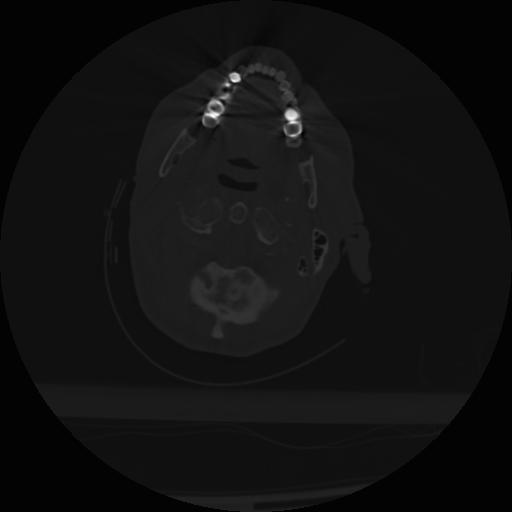

22 ANGIO,CE,Vol,0.5,ANGIO,,